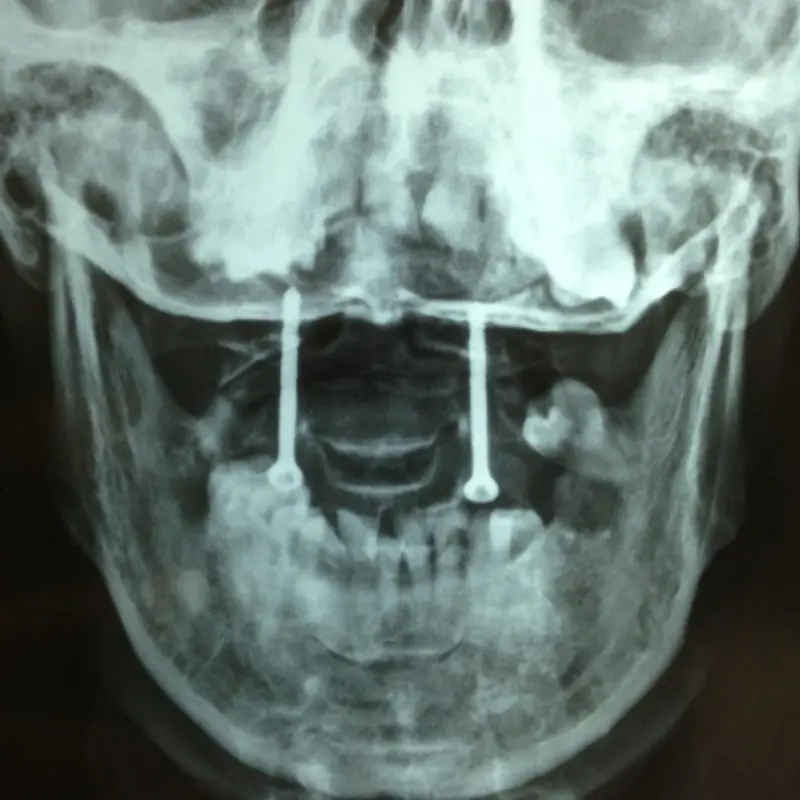

C1-C2 Transarticular Screw